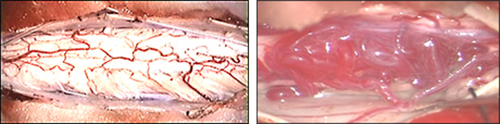

(図5)手術中写真:左は脊髄の正常血管、右は脊髄動静脈奇形により脊髄の血管(静脈)が拡張しています。全ての血管を処置するのではなく、シャント部を探し出しそこを遮断します。